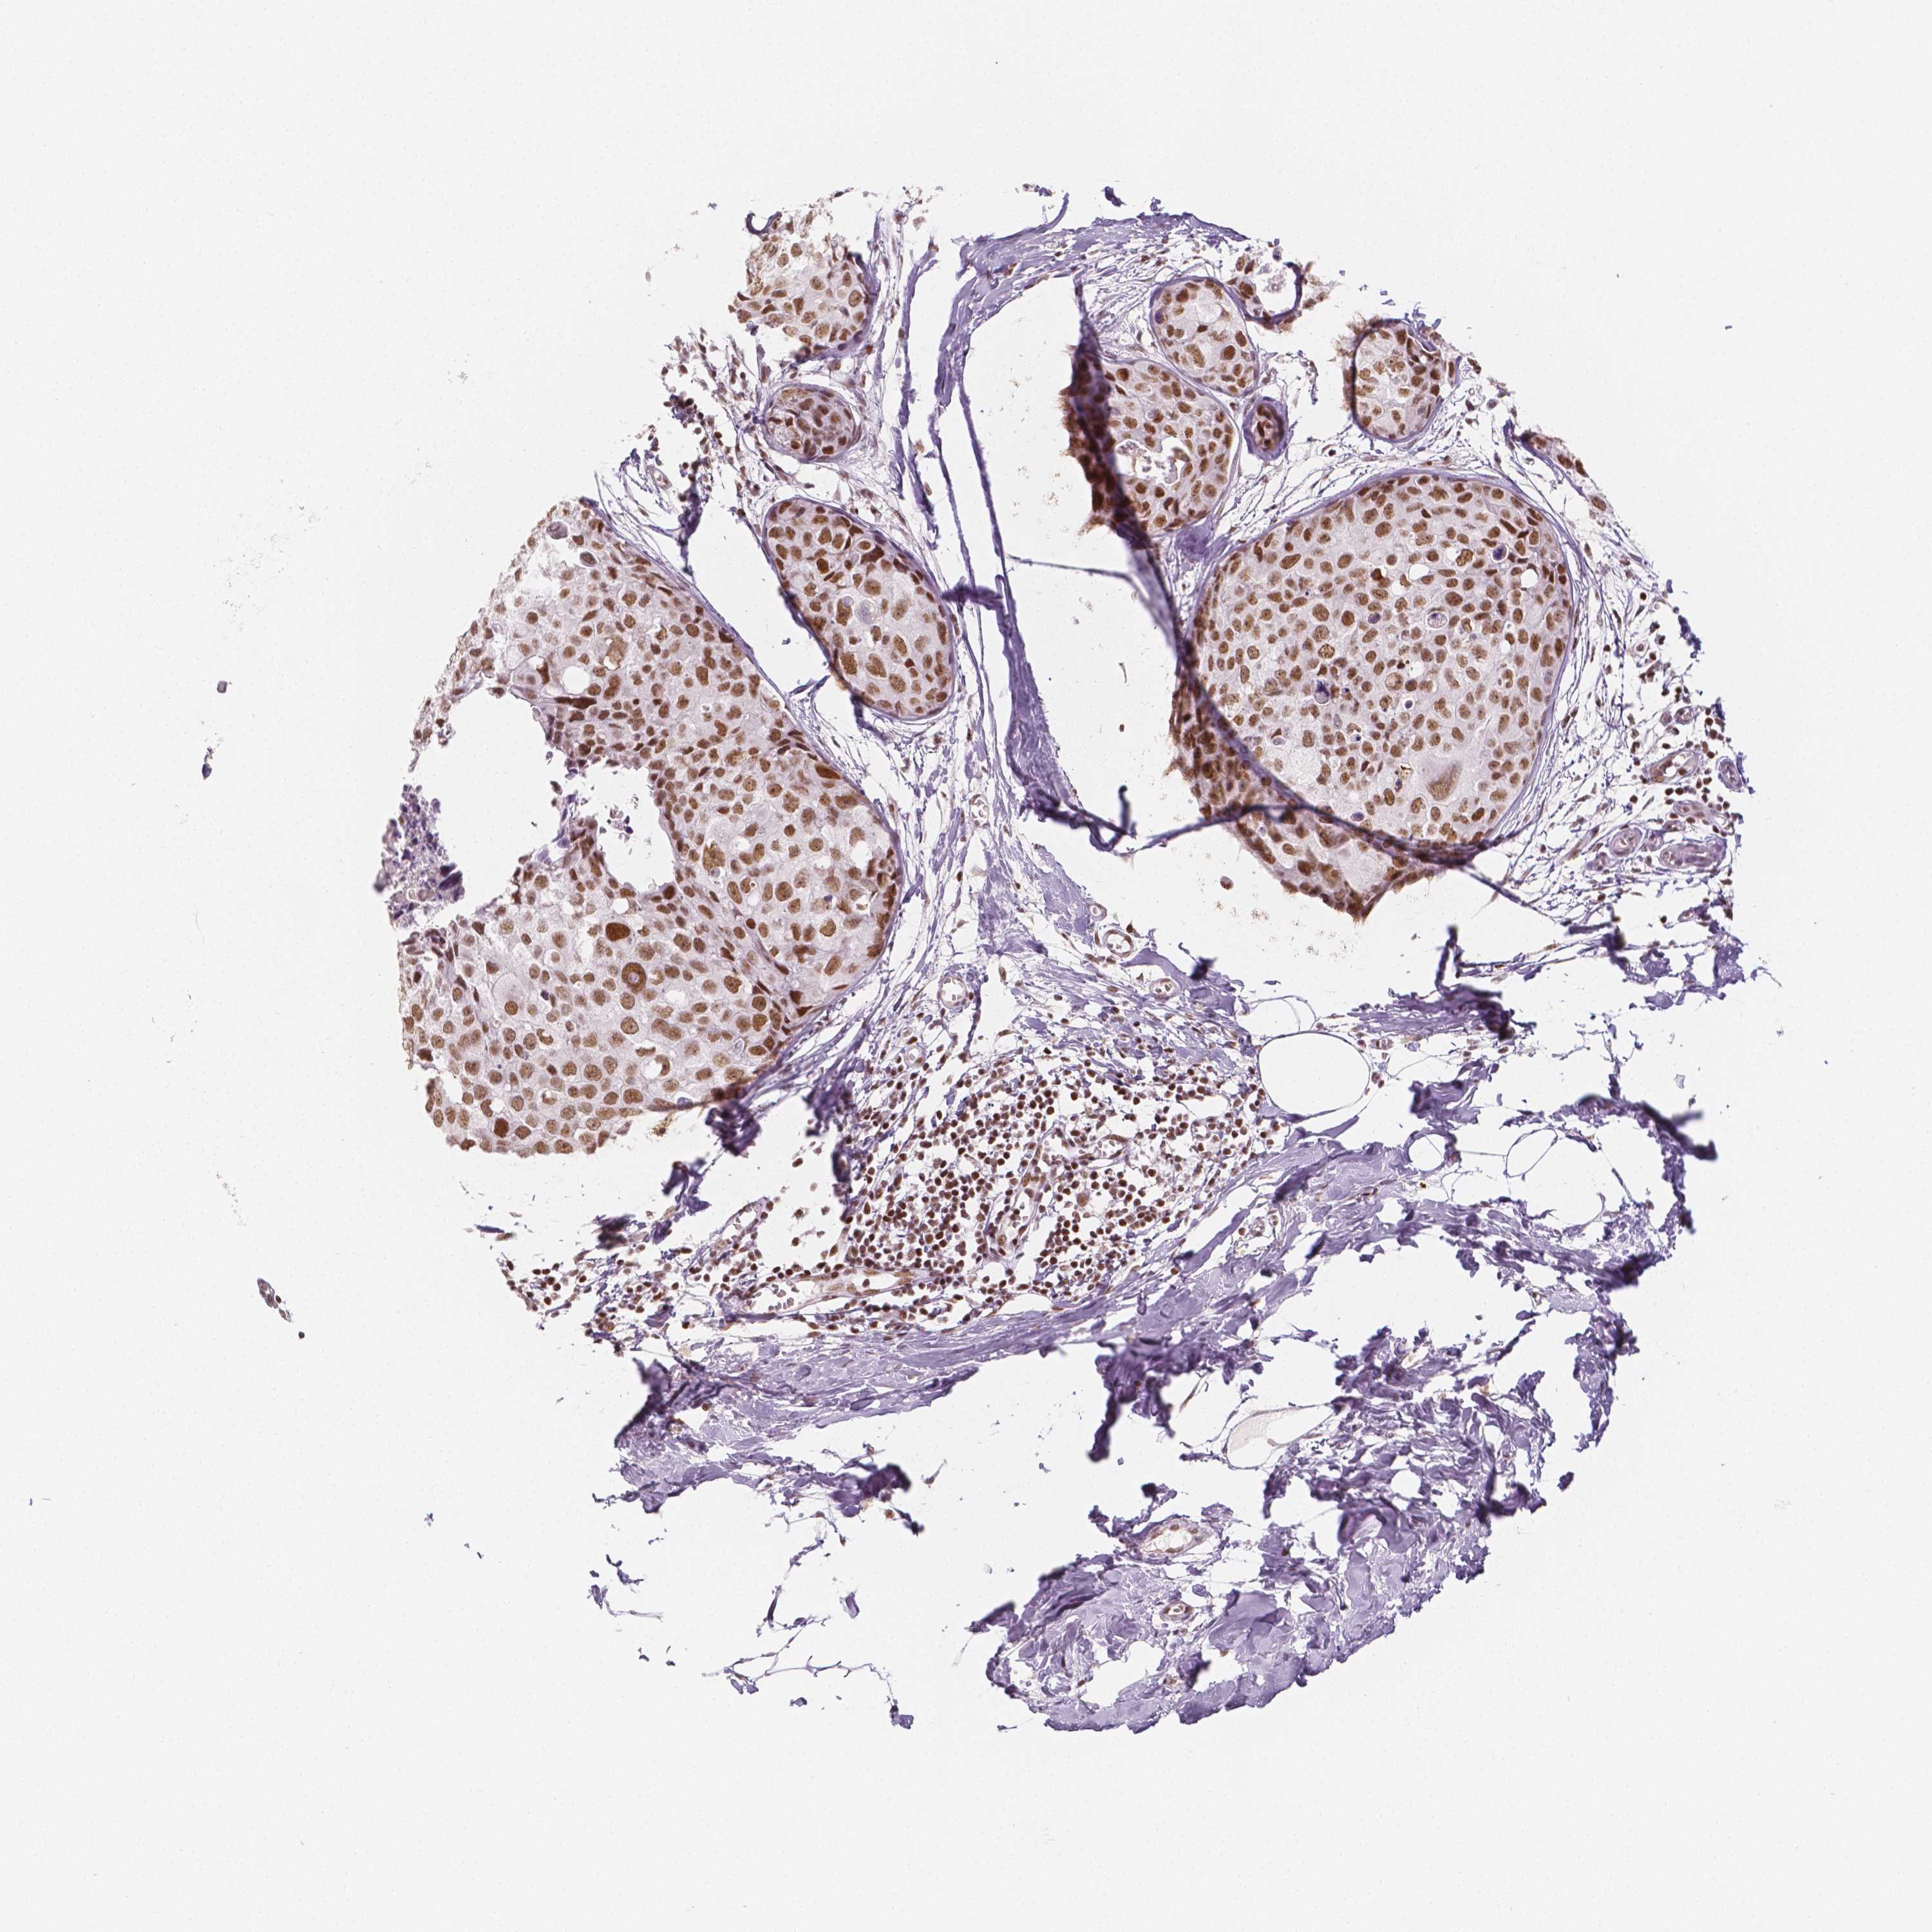

HDAC1

CANCER BREAST CANCER Show tissue menu

BRCA TCGA BRCA VALIDATION PROTEIN EXPRESSION